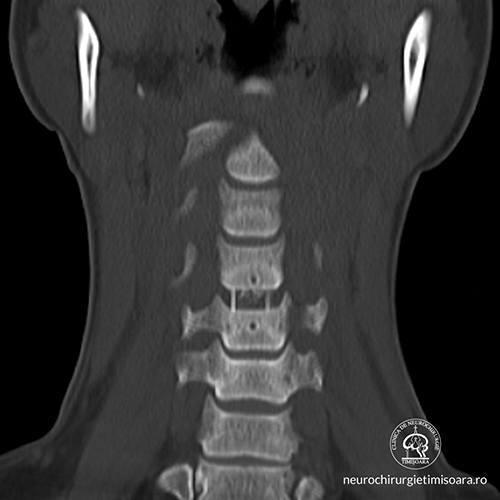

Patologia coloanei vertebrale